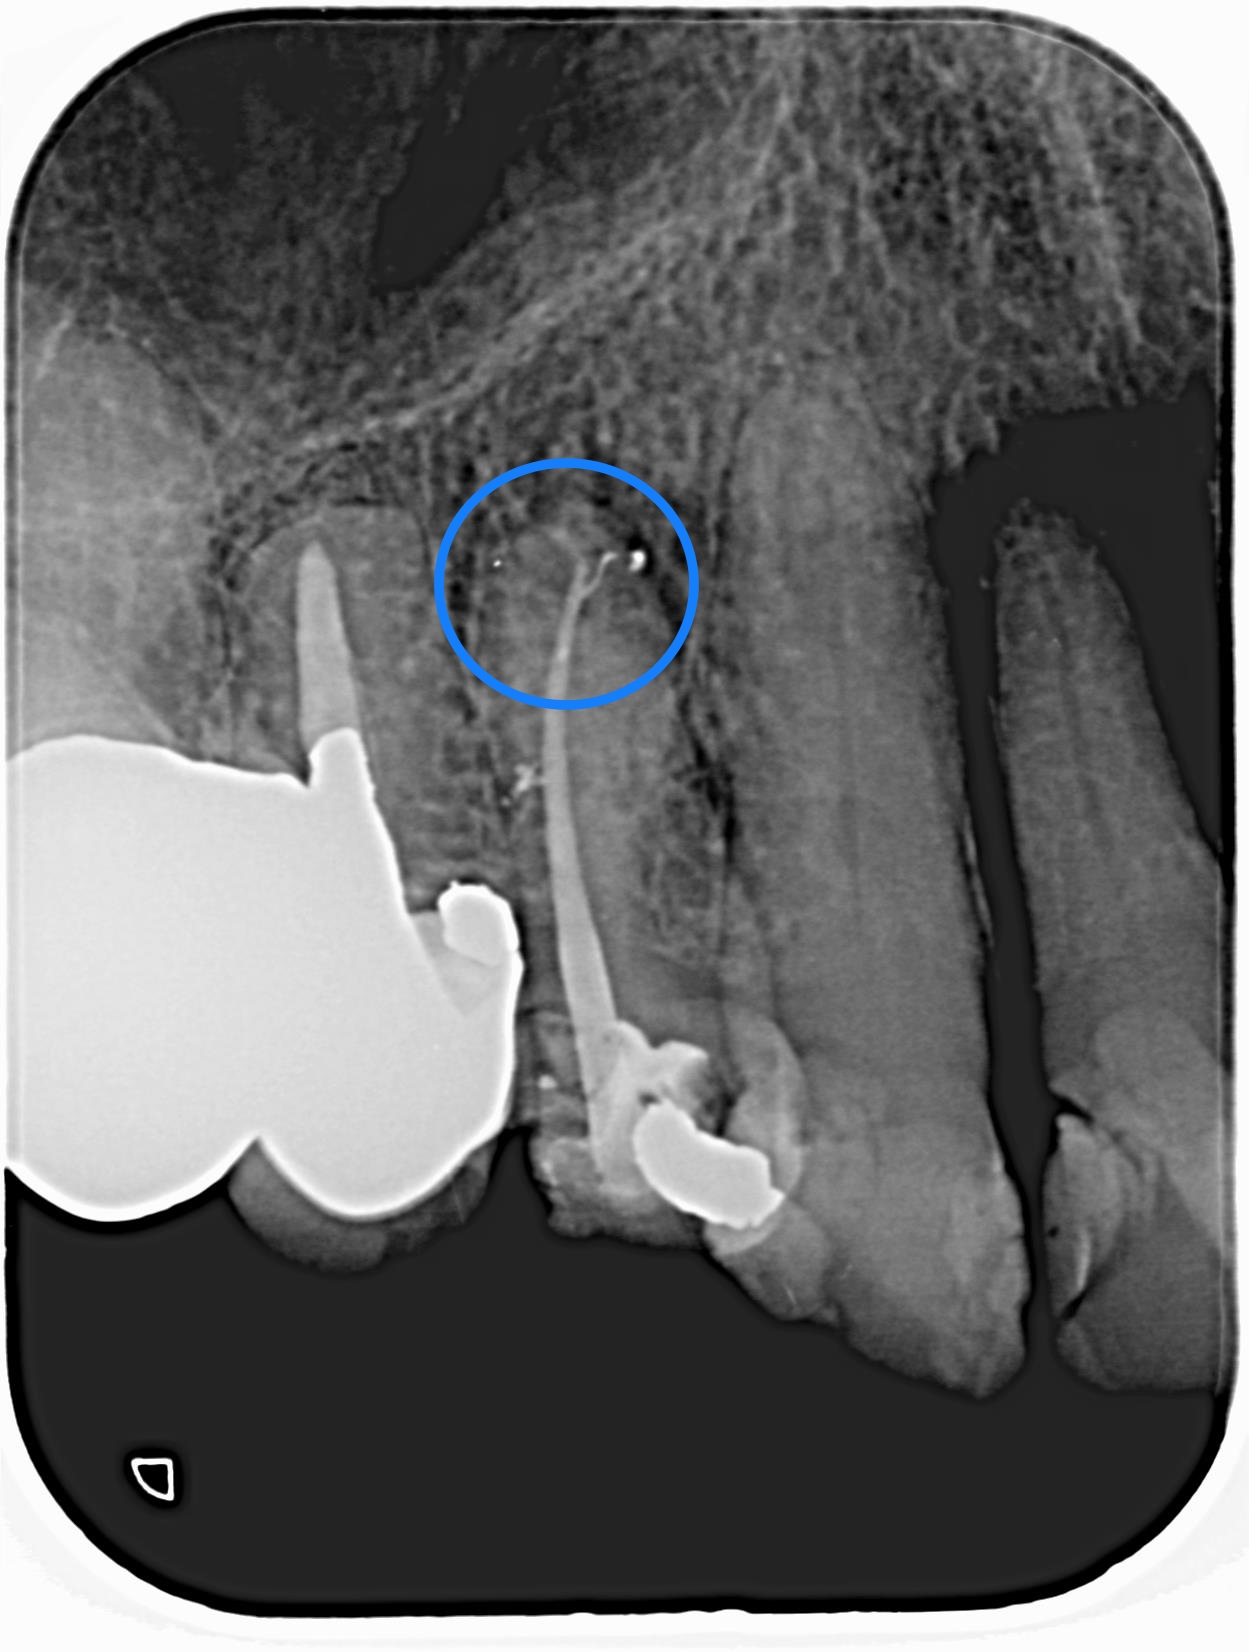

写真の丸印の部分を見ると根っこの先っぽがなんだか枝分かれしています。

根管治療がうまく行くと、たまにはこんな感じでレントゲンに映ることがあります。

歯の神経は一本で綺麗に走行しているのではなく、得に先っぽで網目状に枝分かれしています。

このことが根管治療の確実性を妨げている要因の一つとなっています。